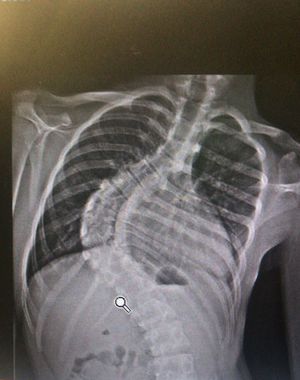

Scoliosis cannot be “cured”, although it can be corrected or the curve can at least be lessened through surgery. Vertebral body tethering or the wearing of a back brace can usually slow the progression of the curve if worn during years of major growth and puberty.

I believe progression can be halted, hence the screening but not reversed.